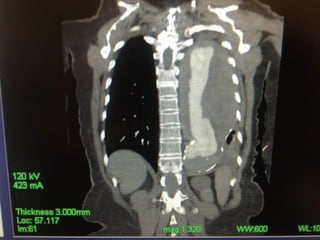

• Preoperative CT 1mm imaging to include pelvisPreoperative CT 1mm imaging to include pelvis